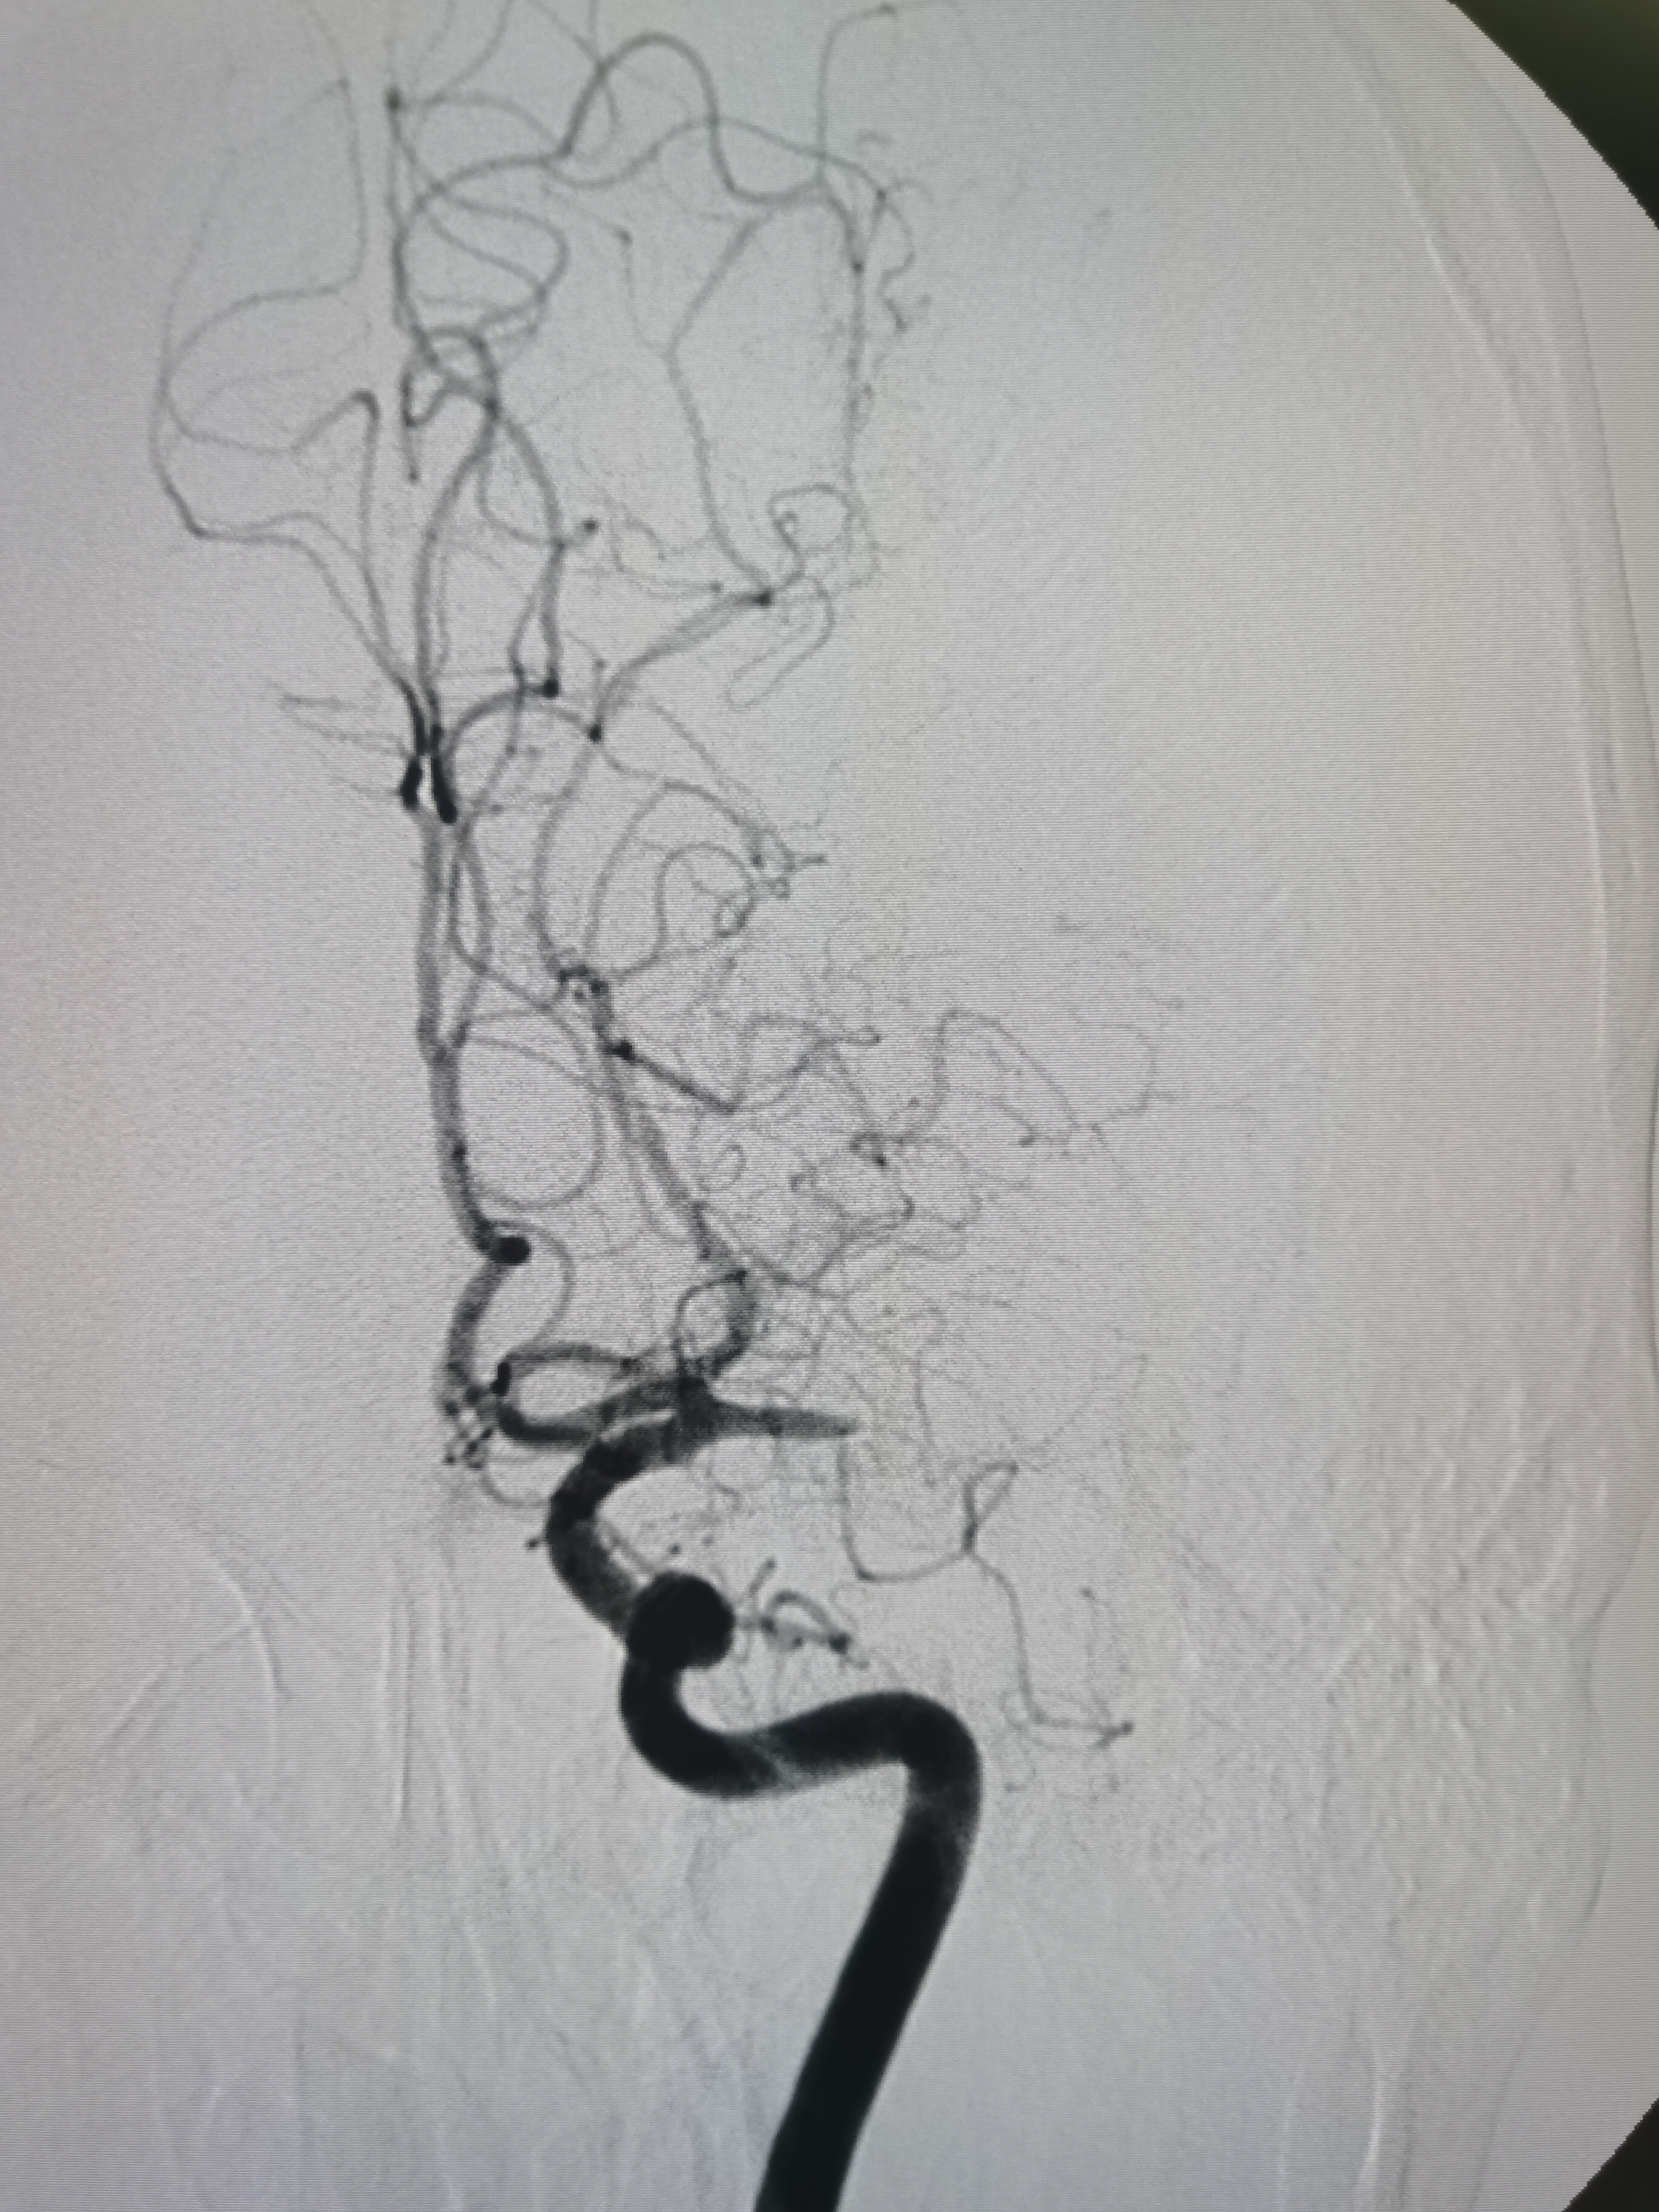

左侧颈内动脉起始部正常。

左侧大脑中动脉闭塞,胚胎型大脑后动脉。

动脉晚期可见软膜支代偿远端血供。